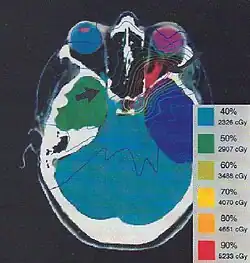

Typically, medical imaging is used to form a virtual patient for a computer-aided design procedure. A CT scan is often the primary image set for treatment planning while magnetic resonance imaging provides excellent secondary image set for soft tissue contouring. Positron emission tomography is less commonly used and reserved for cases where specific uptake studies can enhance planning target volume delineation.[9] Modern treatment planning systems provide tools for multimodality image matching, also known as image coregistration or fusion. Treatment simulations are used to plan the geometric, radiological, and dosimetric aspects of the therapy using radiation transport simulations and optimization. For intensity modulated radiation therapy (IMRT), this process involves selecting the appropriate beam type (which may include photons, electrons and protons), energy (e.g. 6, 18 megaelectronvolt (MeV) photons) and physical arrangements. In brachytherapy planning involves selecting the appropriate catheter positions and source dwell times [10][11] (in HDR brachytherapy) or seed positions (in LDR brachytherapy).

The more formal optimization process is typically referred to as forward planning and inverse planning.[12][13] Plans are often assessed with the aid of dose-volume histograms, allowing the clinician to evaluate the uniformity of the dose to the diseased tissue (tumor) and sparing of healthy structures.